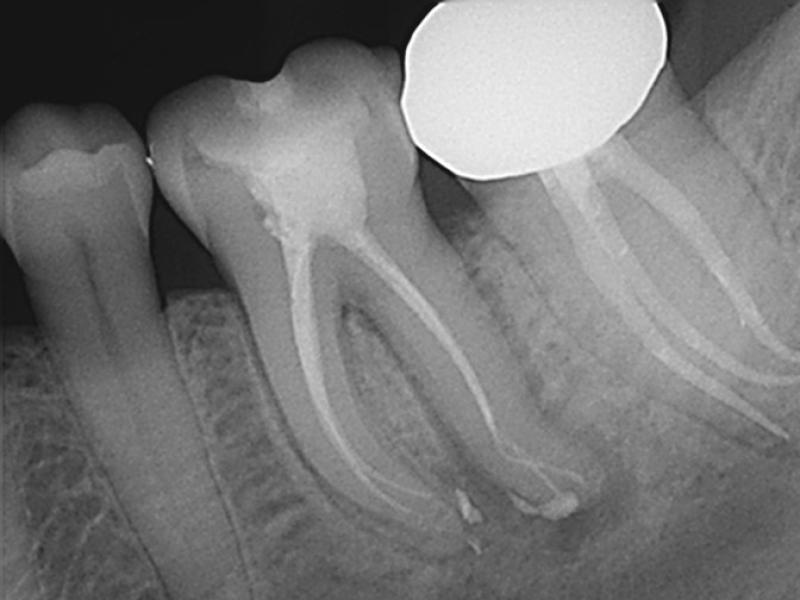

Pre-Op